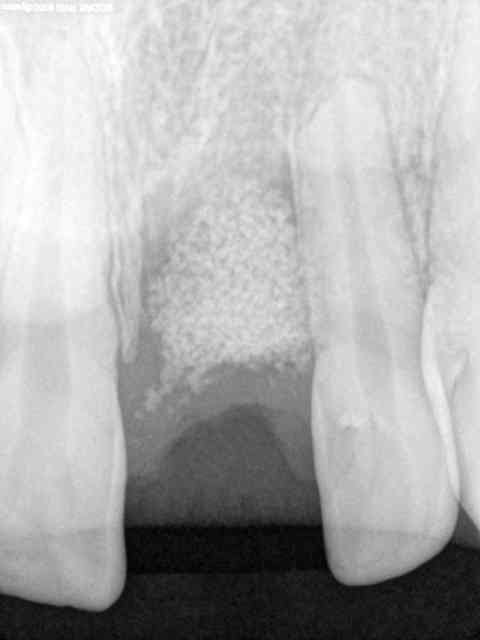

bon une petite ROG (jeamba...)

21 fracturée suite à choc

avulsion

rtr

prf

lambeau tracté coronairement par dessus et collage.

Devinette : dans combien de temps pour l'implant

Je dirais pas avant 6 mois et je suis certain que tu retrouveras une bouillie fragile, autrement je te donnerais définitivement la réponse le 20 mai date à laquelle je poserai l'implant sur le site de la 12 . ROG faite le 20/11/2009.

le problème du beta TCP c'est qu'au bout de six mois, même si tu as une sensation d'os greffé suffisamment dur, il peut se "dégranuler" en fonction de ton forage et de la forme de ton implant...

Ton temps d'attente doit être minimum de 6 mois, et sauf dans le cas où tu aurais une corticale vestibulaire et palatine épaisse sur lesquels tu pourrais avoir un minimum d'ancrage, je te conseille d'attendre 9 mois minimum.

Pour avoir fait ma thèse sur LA PRF(R), c'est pratique, mais ca n accelerera pas ta cicatrisation osseuse, juste épithelioconjonctive.